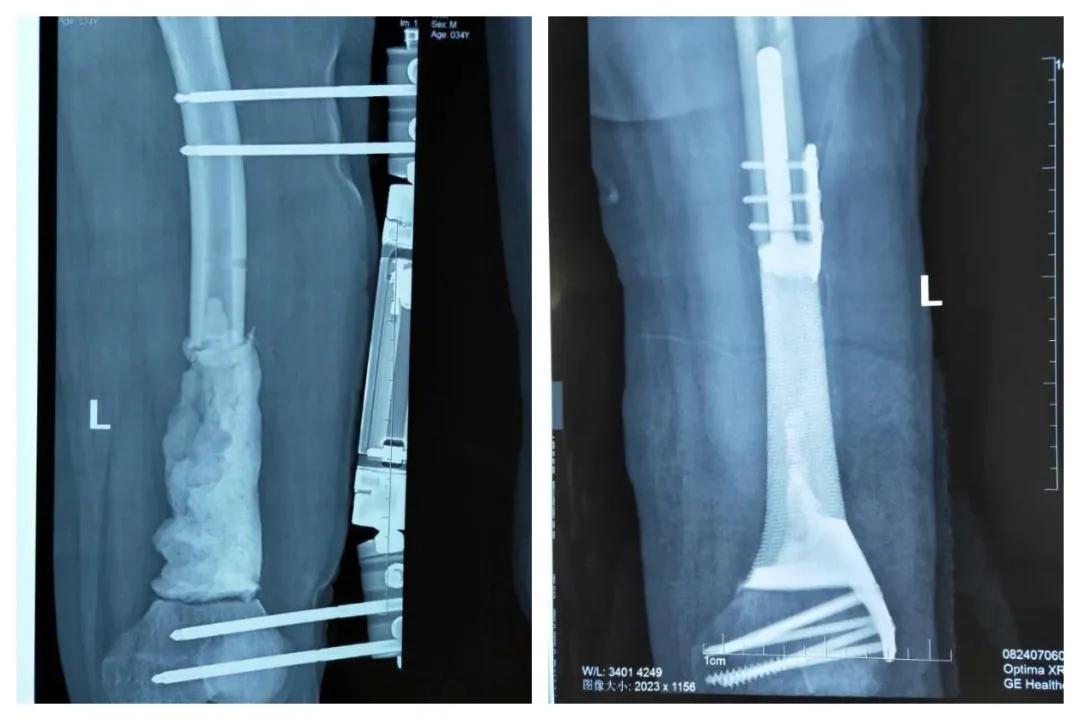

左股骨瘤段骨切除骨水泥占位器植入骨折外固定及术后图片

手术由创伤骨科主任王金山主刀,据王金山介绍,张先生的手术分两次进行。第一次术中把肿瘤切除后旷置,依据CT扫描结果定制3D打印假体,在四周以后进行假体置入术。手术最大难度是肿瘤段骨完整切除,关键技术是诱导膜技术和私人订制3D打印假体。3D打印假体放入后,诱导膜促进骨质再生及修复,手术才能成功。做好充足的手术预案后,在麻醉科的协助下,创伤骨科团队成功将肿瘤切除,并将3D打印个性化定制的钛合金假体完美置入。此例手术由创伤骨科自主完成,该术的成功开展,标志着创伤骨科在应用3D打印技术实施骨肿瘤的个性化治疗中取得了新突破。

经过术后抗感染治疗,患者切口愈合良好,没有出现感染症状,骨折段重建稳定,目前患者指标一切正常,并能下地负重行走。